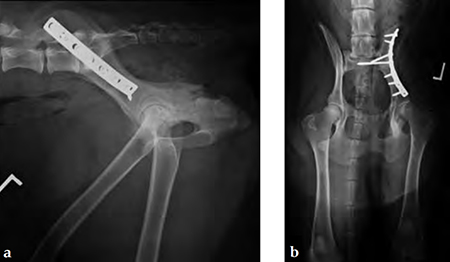

A 4-year-old Gordon setter suffered a road traffic accident and sustained multiple pelvic fractures.

(Case provided by Michael Kowaleski, North Grafton, USA)

A 7-hole 3.5 mm LC-DCP was applied and two screws were inserted into the sacral body to improve fixation strength in the cranial ilial segment. This bone is quite thin thus note that the screws #1 and #2 are quite short, screws #3 and #4 are the sacral screws and are much longer; the fracture is between screws #4 and #5 (see figure 4a-b)). The opacity on midline in the x-rays is a urinary catheter.